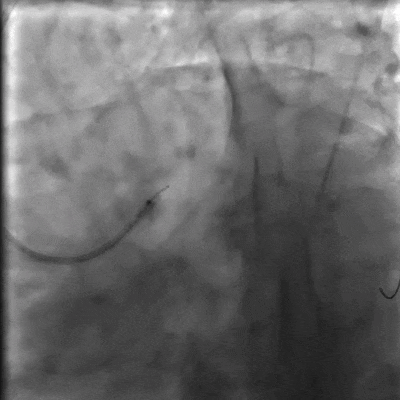

结合患者病史及心电图改变,决定行LCX闭塞病变PCI术。使用Sion blue工作导丝、2.0×15mm预扩球囊进行预处理,血流达到TIMI Ⅰ级,但出现慢血流现象(视频4-5)。

视频4-5 手术经过,出现了慢血流现象

给予本病例患者冠脉内腺苷治疗,以改善冠脉血流。患者心率从80次/分减慢到53次/分,呈一过性变化,血压未受影响,未发生传导阻滞,未诉头晕等不适,血流较前有改善(视频6)。

视频6 冠脉内注射腺苷后图像

再次给予120ug腺苷后,在LCX植入2.75×33mm药物洗脱支架,血流TIMI Ⅱ级。再次冠脉内给予腺苷120ug后,血流达到TIMI Ⅲ级。

视频7-9 LCX植入支架,血流改善